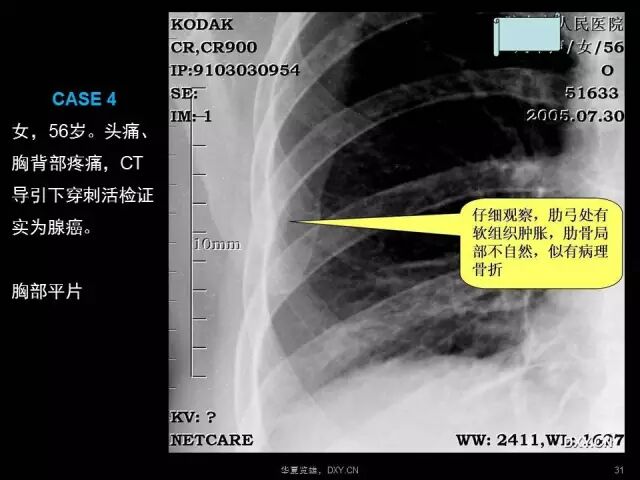

肺炎、肺癌、肺结核在影像学上的征象往往千变万化。